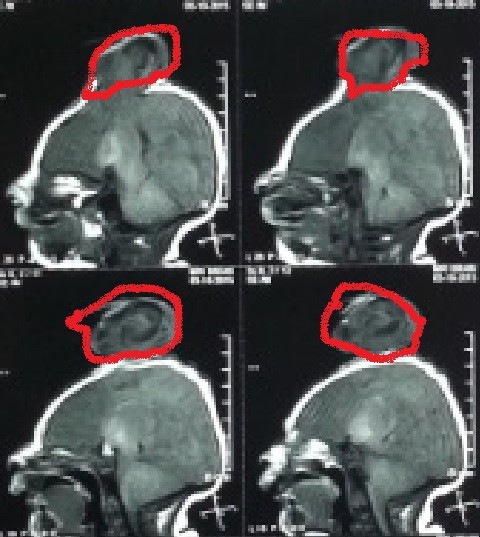

صور لحالة كاملة تم متابعتها منذ الأسبوع الأول من الولادة وحتي عمر ثلاث سنوات لطفل يعاني من قيلة مخية سحائية كبيرة .